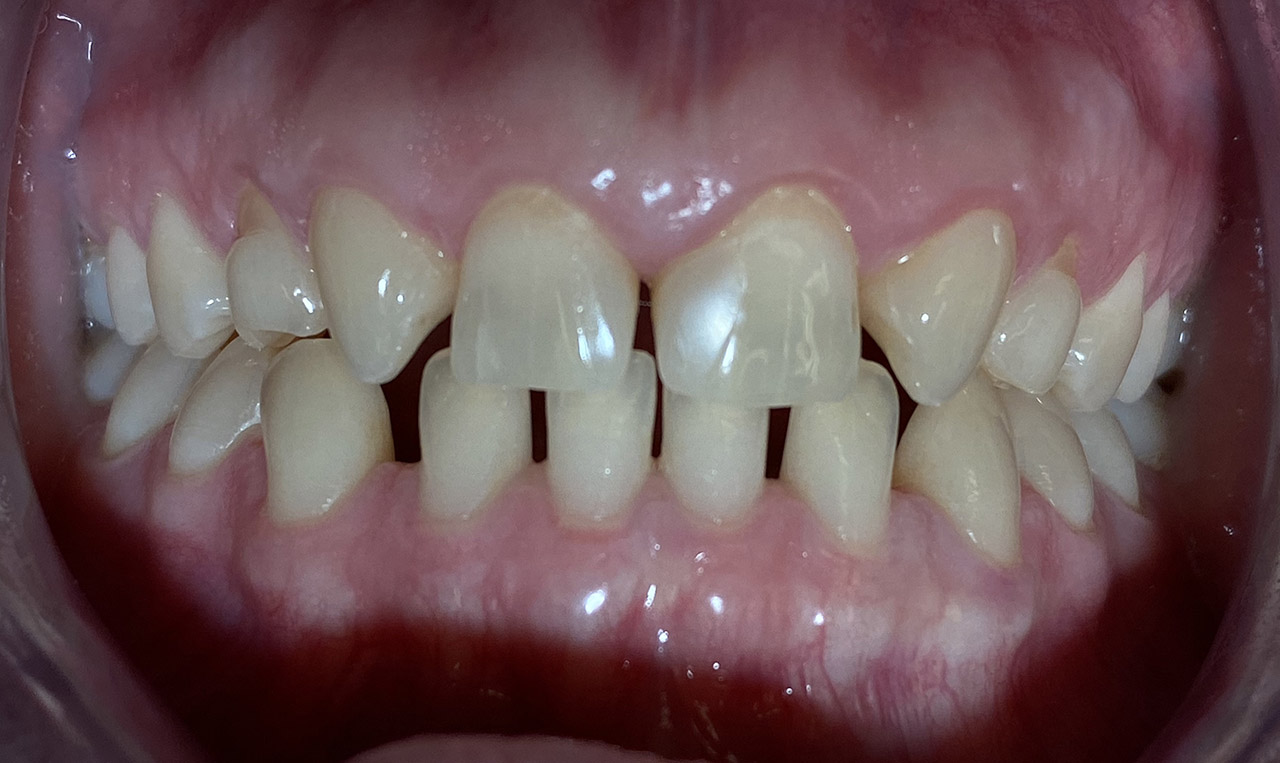

Aplasien/Nichtanlagen, dadurch bleibende Milchzähne, Diasteme/Zahnlücken,

Bleaching/Bleichen, Positionierung der Zähne/Kieferorthopädie (Dr. Maija Eltz), Verblendung mit Veneers/Keramikschalen.

Vorher / Nachher Vergleich mit Slider